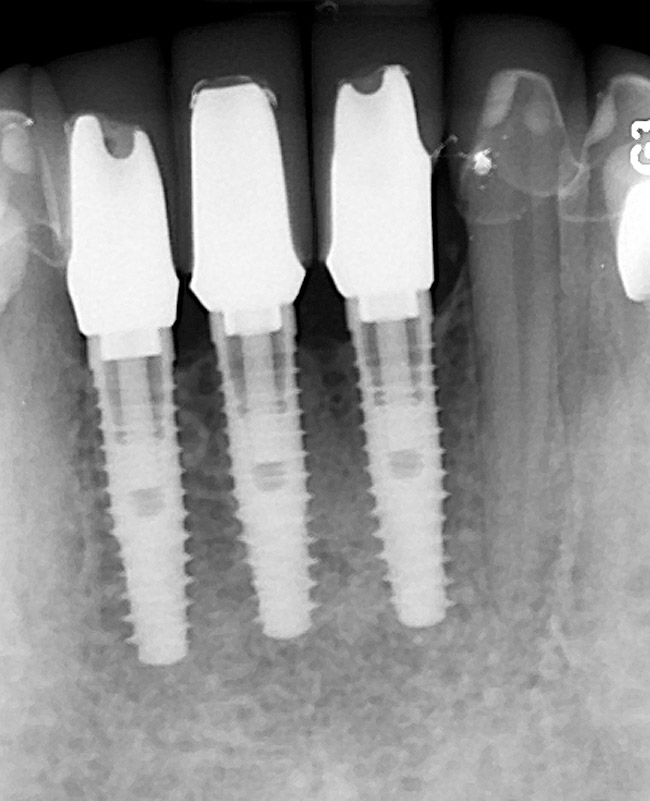

Six months later, the periodontist prepared osteotomies and placed three 3.25-mm x 13-mm implants using a vacuum-formed surgical guide fabricated by the restorative dentist (using a cast of the provisional bridge as a guide, as described by Block et al16); healing abutments were placed simultaneously. A post-implant radiograph confirmed good implant alignment with the pontics of the provisional from teeth Nos. 22 through 28 (Figure 6).

Figure 6  Confirmed ideal implant alignment with pontics in provisional bridge from Nos. 22 through 28—post-placement periapical view.

Figure 6

Figure 9: Implants supporting zirconia abutments and crowns, site Nos. 24 through 26—periapical view.

Figure 9